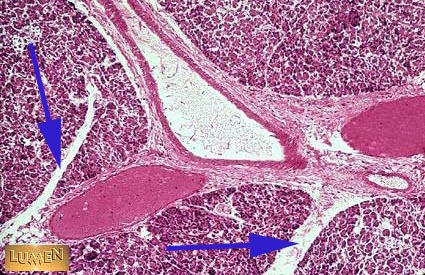

What is this structure in the pancreas?

Connective tissue septa